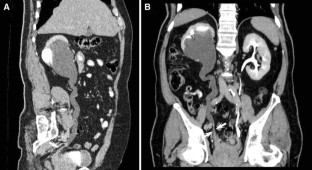

The combination of EU + CT correctly diagnosed 38 out of the 39 cases with a sensitivity of 97%. Correct diagnosis was established in all malignant cases (n = 17) but one benign case consistent with blood clots in the upper urinary tract was incorrectly diagnosed as a multicentric urothelial carcinoma. Sensitivity, specificity, and accuracy for the diagnosis of the underlying cause with EU + CT was 100%, 95%, and 97%, respectively. The final diagnoses were: urothelial carcinoma (n = 10), stone disease (n = 10), bladder tumor (n = 4), benign post-treatment ureteral stenosis (n = 4), ureteral invasion (n = 3), benign bladder disease (n = 2), urinary tract infections (n = 2), crossing vessels (n = 1), ureteropelvic junction obstruction (n = 1), retrocaval ureter (n = 1), and blood clots in the upper urinary tract due to bleeding renal metastasis from lung cancer (n = 1).

Combined EU and CT study allowed correct diagnosis of the underlying cause of delayed excretion or upper urinary tract dilatation in 97% of cases. The combination of EU and CT provides diagnosis reducing time and radiation.